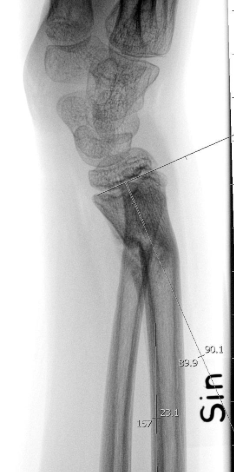

Distal radiusfyseolys <10 år flickor, <12 år pojkar (”dorsalbockad”)

Gränsvärde | ≤25º. ≤ ½ benbredd ad latus. (Mät relativt radius längsaxel på sidobild). |

Distal radiusfyseolys >10 år flickor, >12 år pojkar (”dorsalbockad”)

Gränsvärde | ≤15º. ≤ 1/4 benbredd ad latus dorsalt. (Mät relativt radius längsaxel på sidobild). |